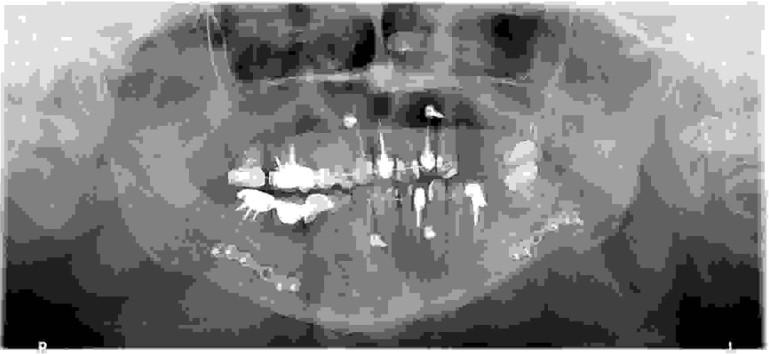

Poniższe zdjęcie pantomograficzne zostało wykonane bezpośrednio po zabiegu chirurgicznym: Przeprowadzony zabieg to:

Pytanie 71